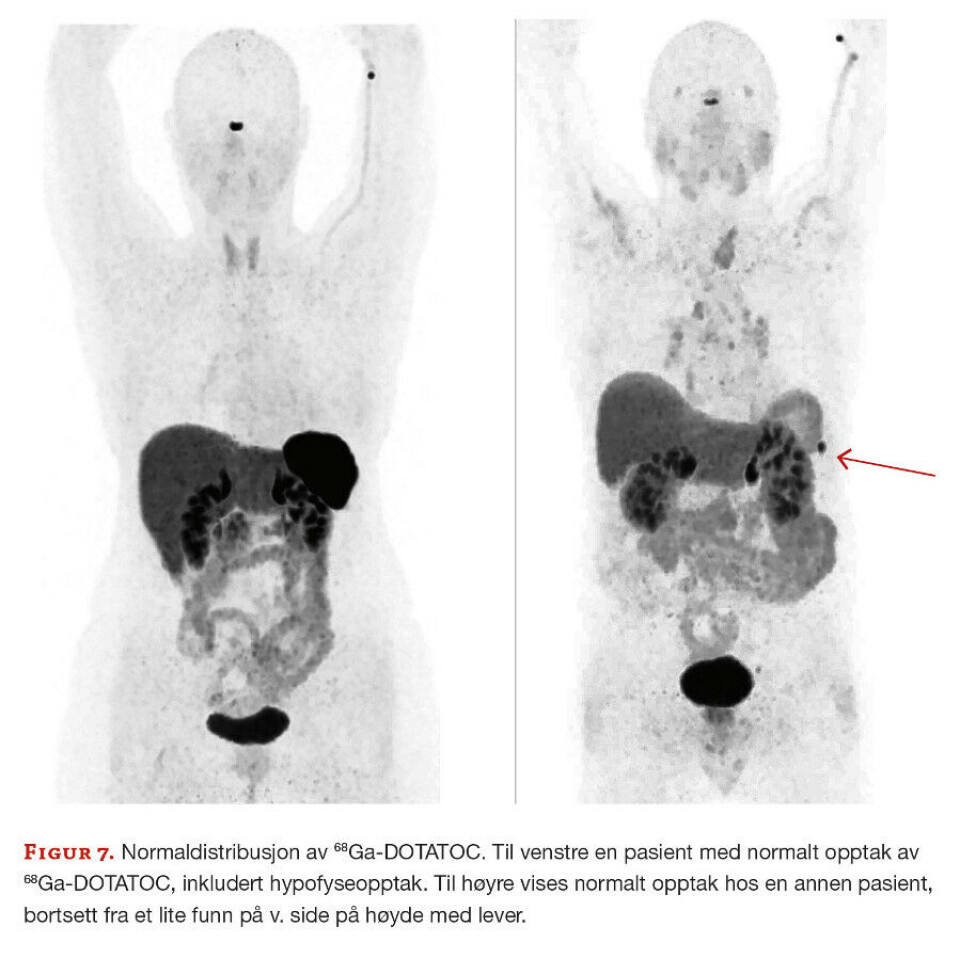

Generelt varierer normalt opptak i ulike organer og vev fra person til person, slik figur 7 illustrerer. Nukleærmedisiner som tolker bildene, må kjenne til hvordan det enkelte radiofarmaka distribueres i organismen for å kunne tolke bildene riktig.